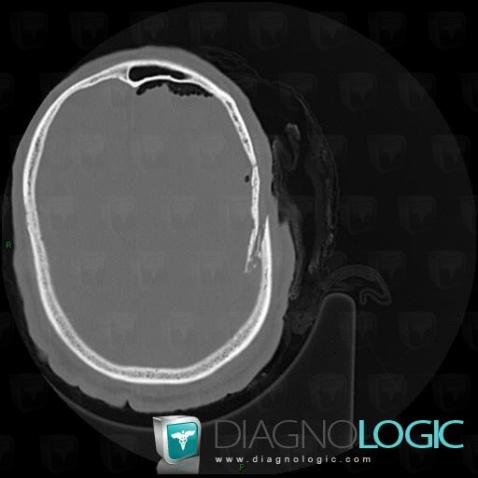

Fracture, Voute-crâne, Os temporal, Scanner

Voici les informations spécifiques à l'image clé ci dessus:

- Diagnostic Fracture, Localisation(s) Voute du crâne, comportant les gammes Os temporal, comportant les gammes